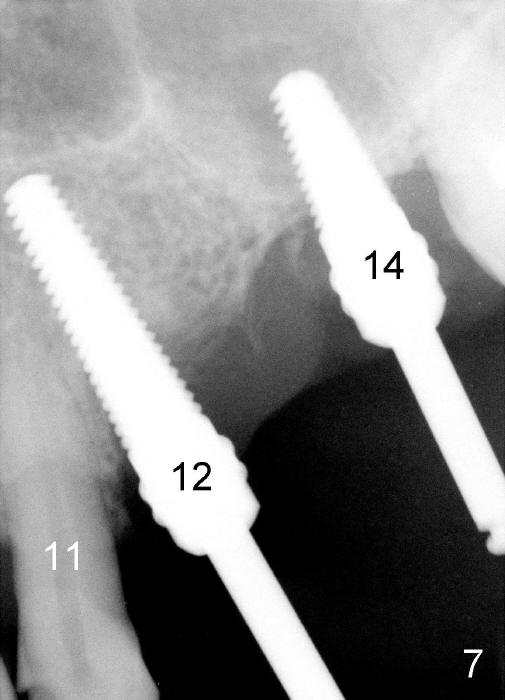

Initially the osteotomy is established with drill/reamers alternated with taps in the septum near the palatal socket. When a 4.5x14 mm tap (Fig.6 T; Fig.7: #14) is inserted, the sinus floor is perforated, but the sinus membrane is intact. When 7x14 mm tap is inserted, the sinus membrane is perforated in the buccal aspect of the osteotomy. The latter is repaired by placement of collagen dressing and then bone graft and membrane again (sandwich). The osteotomy is shifted to the palatal socket by using 5x14 and 6x14 mm taps. When the last tap is removed, the small area of the buccal aspect of the osteotomy is also found to be perforated, but the membrane is intact. When a 6x14 mm implant is placed (Fig.8), the coronal end is close to the middle of the socket (buccopalatally, due to angulation of the palatal socket).

Placement of immediate implant at the site of #12 is relatively easy. Adjustment is more or less mesiodistal. A 2 mm pilot drill (Fig.6 P) is found close to the root of the tooth #11 (red dashed line). The osteotomy is then moved distally (Fig.6 arrow). When 4.5x20 mm tap (Fig.7: #12) and 4.5x17 mm implant (Fig.8 I) are placed, there is distance from the root of the neighboring tooth. Insertion torque of the both implants is >60 Ncm. Abutments are placed (A in Fig.8) for immediate provisional.